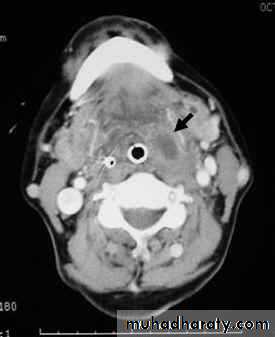

Parapharyngeal Abscess

A suppurative infection of the parapharyageal space.

1. Tender and firm swelling in the upper part of the neck.

2. The pharyngeal wall and tonsil are pushed medially.

Ultrasound of the neck can differentiate between cellulites and abscess collection.